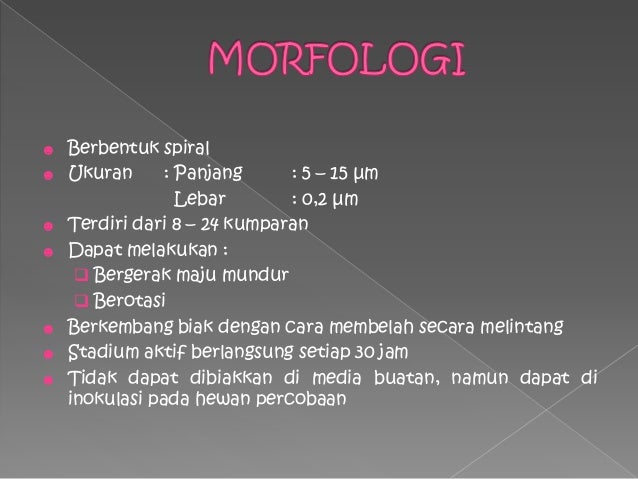

Karakteristik treponema pallidum, morfologi, habitat / Biologi | Thpanorama - Jadikan diri Anda lebih baik hari ini!

Karakteristik treponema pallidum, morfologi, habitat / Biologi | Thpanorama - Jadikan diri Anda lebih baik hari ini!